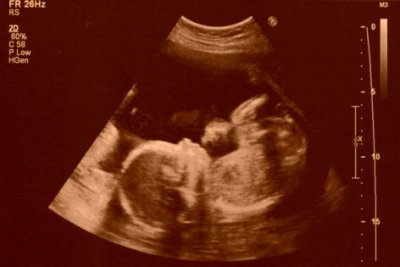

Ultrasonografi (ultrason) yöntemi röntgen ışını içermeyen bir yöntemdir, sadece ses dagalarını kullanarak çalışır. Bu nedenle hamile veya diğer insanlarda dokuya bir zarar vermesi beklenmez. Gebelik sırasında yapılan ultrason muayenelerinin bebek (fetus) üzerinde herhangi bir yan etki riski taşımadığını gösteren bir çok bilimsel araştırma vardır. Ultrason çok uzun yıllardır hamilelik takibinde kullanılan bir yöntem olduğu için bebek üzerine olası etkileri konusunda çok fazla tecrübe vardır. Bu tecrübeler ve bilimsel araştırmalar sonucunda bebeğe hiçbir zarar vermediği konusunda bildiriler çoktur.

Her uygulama gibi ultrasonografi uygulamasının da gereksiz yere fazla yapılması hem maliyet olarak hem zaman olarak israf anlamına gelecektir. Bu nedenle sadece gerekli durumlarda ve gerekli sayıda gebelik boyunca uygulanmalıdır. Gebeliğin başından doğuma kadar uygulanan ultrason sayısı hastaya ve gebeliğin durumuna göre değişmekle birlikte ortalama 5 - 10 arasında değişmektedir, bazı gebeliklerde daha fazla da uygulanabilir.